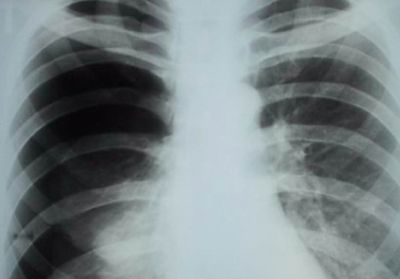

Правостороннее воспаление легкого характеризуется тупой болью в правом боку, локализованной преимущественно в подреберье.

Мнение эксперта

—

При длительном течении заболевания боль ощущается в груди и спине со стороны пораженного органа.